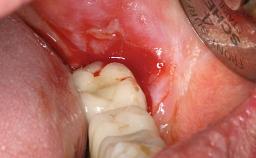

A 73-year-old woman was referred to the Division of Periodontology (University of Geneva School of Dental Medicine) after repeated unsuccessful treatment of a peri-implant infection. She was systemically healthy and did not smoke. The patient’s history revealed that, three years earlier, an immediate implant (Straumann Tapered Effect RN 4.8/4.1; Institut Straumann AG, Basel, Switzerland) had been inserted to replace the upper right central incisor. A metal-ceramic crown had been delivered using an adhesive resin cement. One year later, the patient had consulted another dentist due to discomfort in the soft tissues in the implant region. There was a suppurating peri-implant pocket, 10 mm deep. Peri-implant bone loss and excess luting cement were seen on the radiograph. The situation was treated with non-surgical debridement, amoxicillin, and repeated submucosal irrigation with a chlorhexidine digluconate solution. The patient was referred after the suppuration had persisted for several months.